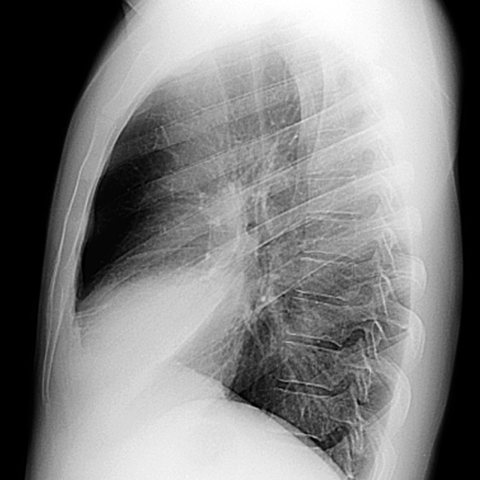

Silhouette Sign, RML Pneumonia (Lateral CXR) [2 of 4]